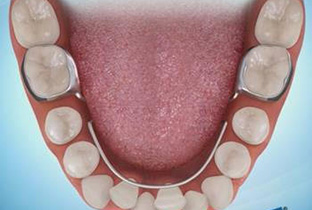

The Herbst appliance is typically used in cases where the overbite is caused by a discrepancy between the size of the upper and lower jaws. The appliance consists of metal rods that are attached to bands placed on the upper and lower molars. The rods are designed to hold the lower jaw forward in a more natural position, which can help reduce the overbite.